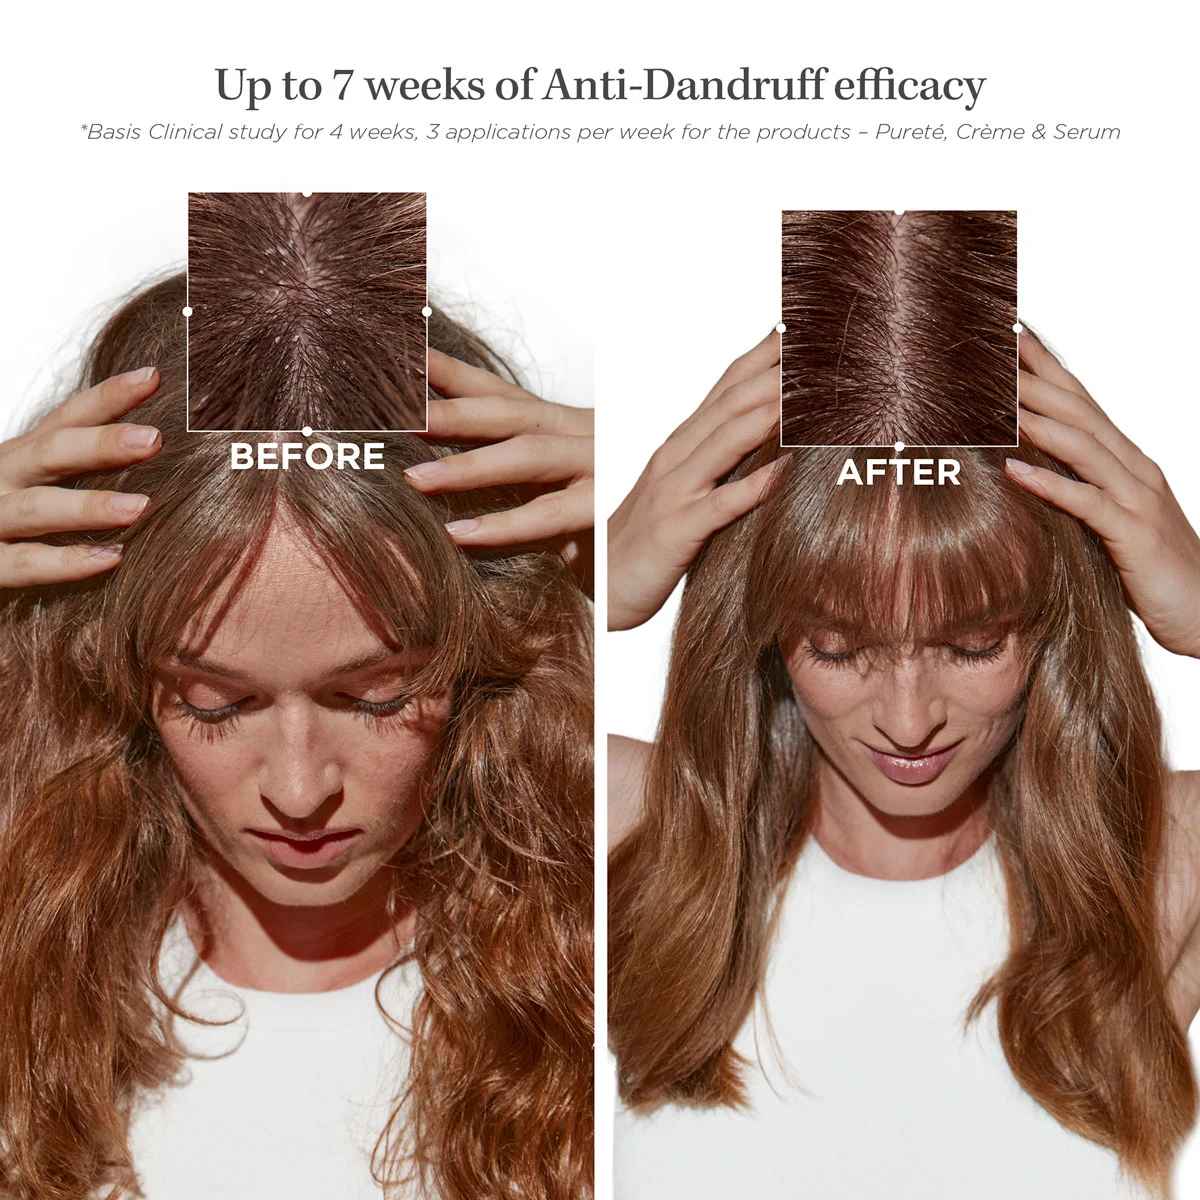

A caring yet breathable foaming formula to remove dandruff while preventing oil build up. Exfoliates instantly and removes visible dandruff, calms scalp sensitivity, balances oil levels, and boosts hair vitality while promising up to 7 weeks of anti-dandruff efficacy.*

*Basis Clinical study for 4 weeks, 3 applications per week for the products – Pureté, Crème & Serum

✔ Up to 7 weeks of anti-dandruff efficacy*

*Basis Clinical study for 4 weeks, 3 applications per week for the products – Pureté, Crème & Serum

Before & After

Before & After

Illustration of the contemplated results obtained after applying: